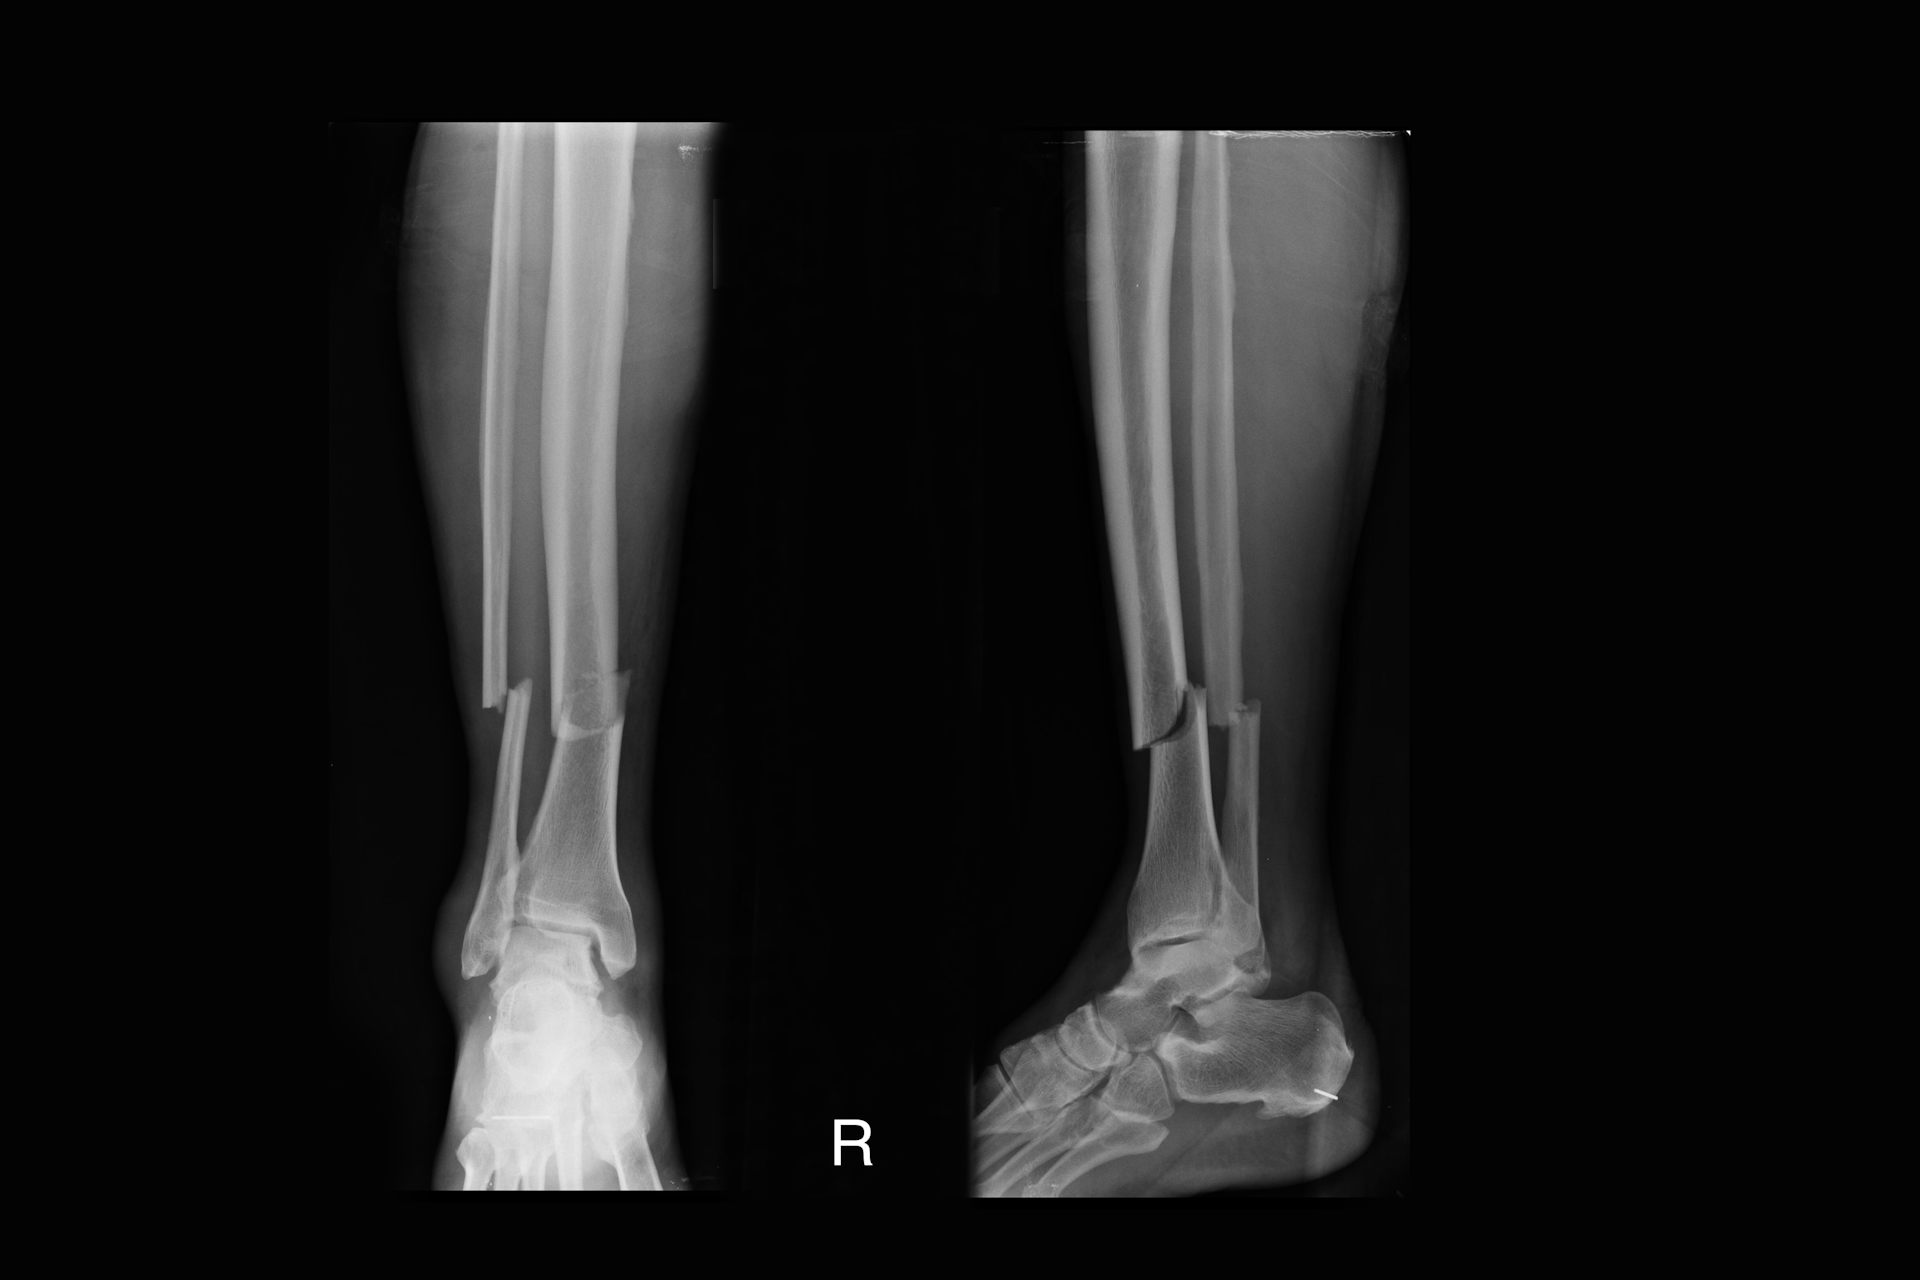

Gebrochene Tibia und Fibula Röntgenaufnahme

x-ray bilder von gebrochenes bein, ap ausblick und seitliche ansicht. – broken leg xray stock-fotos und bilder

X-ray Bilder von Gebrochenes Bein, AP Ausblick und seitliche…

Gebrochene Beinröntgenaufnahmen zeigen Tibia- und Wadenbeinfraktionen.